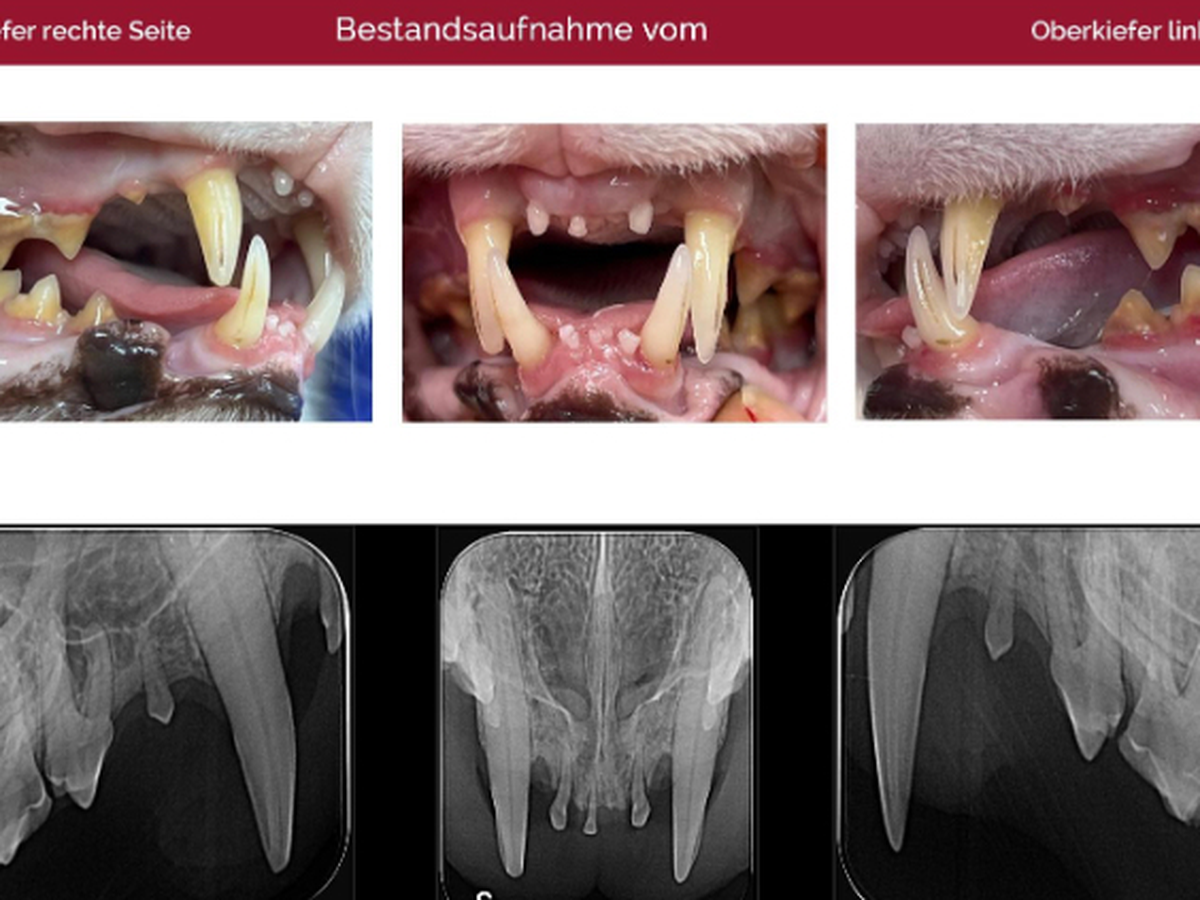

Doch bei der tierärztlichen Kontrolle dann der Schock - seine Zähne waren fast alle nahezu krank oder abgebrochen. Was musste der arme Kerl alles schon erlebt haben…?

Die komplette Zahn-OP hat 2.500 Euro gekostet. Bito hat nun nur noch 4 Fangzähne, aber er kommt damit super zurecht.